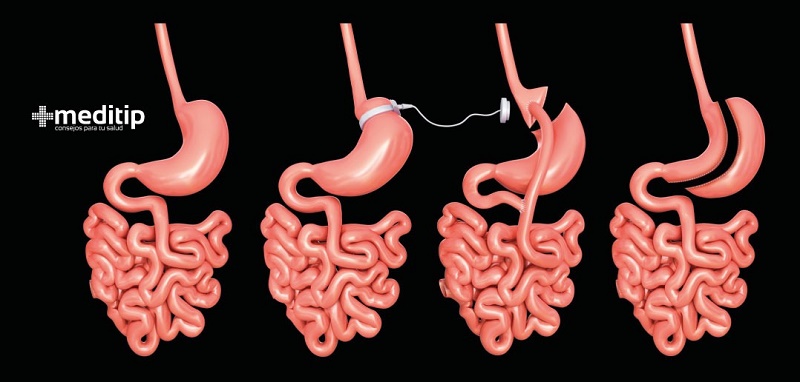

La técnica del balón intragástrico consiste en una esfera de látex llena de suero fisiológico colocado vía endoscópica en el estómago bajo sedación en un ingreso ambulatorio. Su principal efecto es la disminución de la motilidad del estómago reduciendo el tiempo de vaciado tras la ingesta de alimentos y provocando, en la mayoría de los casos, una sensación de saciedad temprana y demorada durante las comidas.

La cirugía bariátrica se dirige a enfermos con obesidad tipo I y II, es decir, que su índice de masa corporal se encuentre entre treinta y treinta y cinco. Las cirugías bariátrica y metabólica son las mejores opciones terapéuticas para este tipo de obesos y han demostrado tener una mayor efectividad transcurrido el tiempo, si bien es fundamental que sirva para que estos enfermos modifiquen sus hábitos hacia otros más saludables, tanto con la dieta como con el ejercicio físico.

La cirugía metabólica también ha constatado su alta efectividad en enfermos que, tras realizarse una cirugía endoscópica de balón, ha recuperado su peso transcurrido un tiempo. El enfermo que se ha realizado una intervención endoscópica de balón, no tiene ningún tipo de contraindicación a la hora de realizarse una cirugía bariátrica.